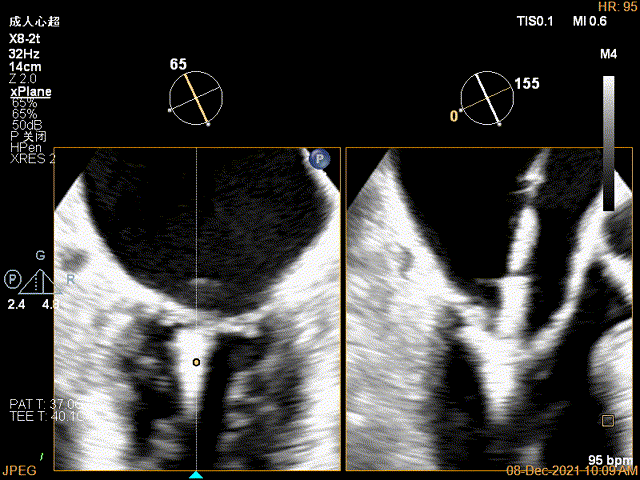

X-plane:下夹子尝试先捕获2区瓣叶

夹子关闭过程中,Color提示2区反流逐渐减少,残余反流位于夹子外侧

x-plane验证前后叶抓捕后bond明显